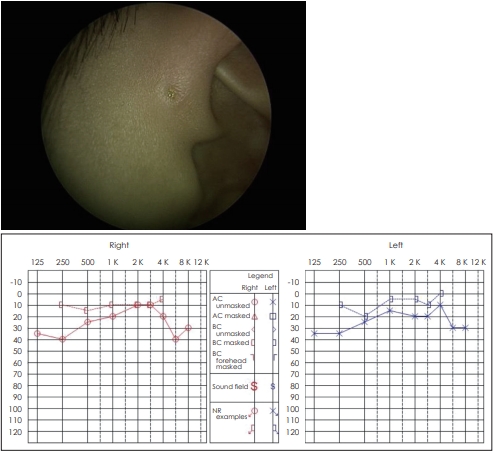

1. 8세 남자 환자가 양측 이루공으로 내원하였다. 선천적으로 우측 안면마비가 있었으며, 이전에 경부에 누공이 있어, 타 병원에서 경부 누공절제술을 하였던 병력이 있다고 하였다. 고막검진 및 임피던스검사는 정상이었으나 순음청력검사가 그림과 같이 측정되었다. 아버지도 양측 이루공이 있으며, 경도 난청이 있다고 호소하였다. 다음 중 이 질환에 대한 옳은 설명은?

① 사례의 순음청력검사와 같이 전음성 난청이 특징적이다.

1. 답 ②

해 설 Branchiootorenal(BOR) 증후군. 상염색체 우성 유전을 보이며, 90%의 환자에서 난청을 동반하며, 이에 더불어 전이개 누공, 전이개부속물, 그리고 경부누공 등의 새열기형과 신장의 이상을 동반할 수 있다. 감각신경성, 전음성 혹은 혼합성 난청 등 다양한 난청 종류가 모두 나타날 수 있다. BOR 증후군의 대표적인 원인 유전자는 EYA1 gene으로 투과도(penetrance)는 100%에 달한다.